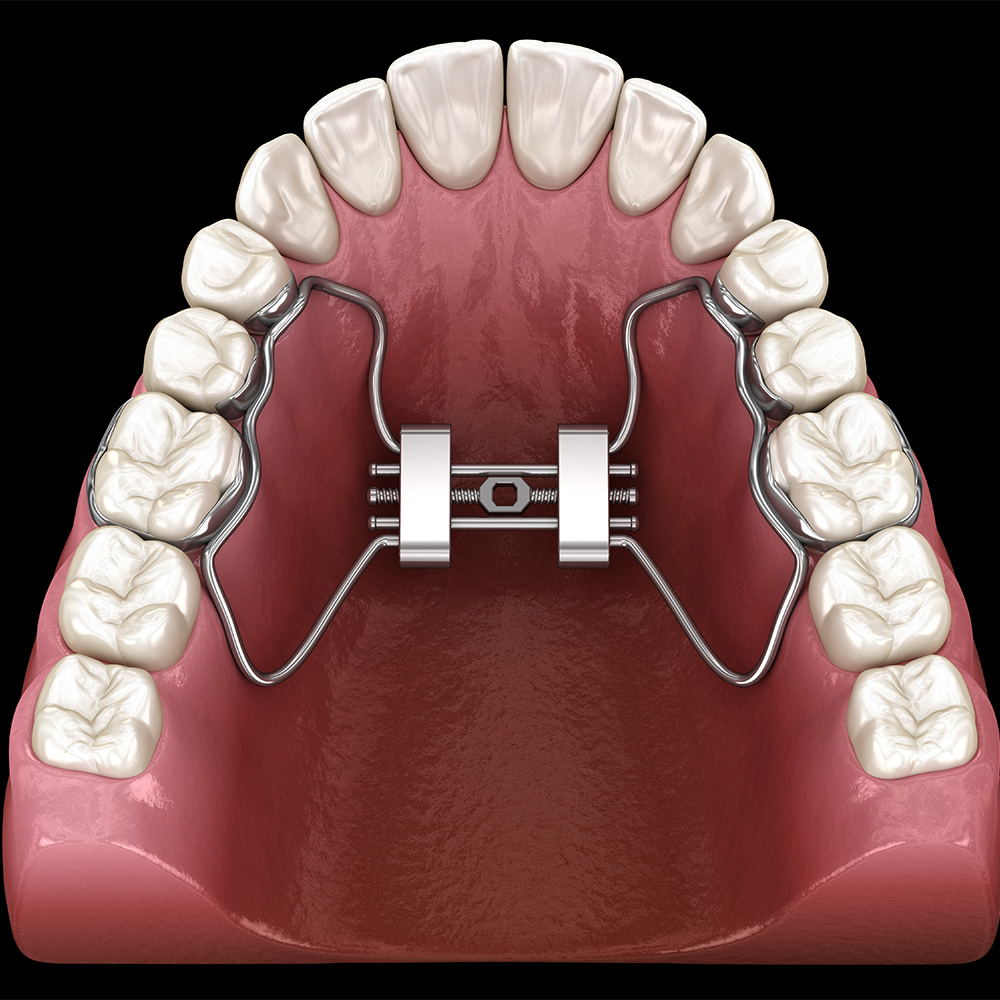

The Role of Palate Expanders in Pre Orthodontics

The palate expander is one of the most powerful tools in pre orthodontics. This device gently widens the upper jaw, creating space for teeth to align naturally while also improving airway function.

Benefits of a Palate Expander:

Improved Sleep Quality: By addressing airway issues, children can enjoy restful sleep and wake up energised.

Reduced Behavioural Issues: Resolving breathing-related sleep disruptions can lead to better focus and mood.

Long-Term Dental Health: Early treatments prevent more invasive orthodontic procedures later, such as extractions or braces.

Balanced Facial Growth: Tools like the palate expander promotes natural, symmetrical development.

Improved quality of Life : kids who have had expansion done reported better quality of life in a random controlled clinical trial . (https://kevinobrienorthoblog.com/maxillary-expansion-improves-childrens-quality-of-life-a-tremendous-new-trial/)

Palate Expander Before and After

Many parents wonder about the potential impact of a palate expander. Palate expander before and after results demonstrate significant improvements in:

- Wider dental arches, allowing for proper tooth alignment.

- Enhanced nasal breathing and reduced mouth breathing.

- Improved facial proportions and symmetry.

These results showcase how early intervention with pre-orthodontics can transform not just smiles but overall health.